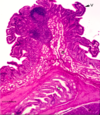

·gall bladder - no muscularis mucosa, submucosa, crypts

From the liver, bile obviously goes through those bile ductules into larger bile ducts that are found in the portal tracts out eventually to the gallbladder. Students confuse the gallbladder with the intestine, or the small intestine. So I’ve put some of the things that are not here, compared to the small intestine.

·There’s not going to be a muscularis mucosa, which you saw in intestine. There’s not going to be a separate submucosa, there’s not going to be crypts, although sometimes there’ll be downgrowths (1) called Aschoff sinuses that are abnormal. And the surface has folds, but these are not really villi.

·And, in addition, if you think about – you’ve seen the abdominal cavity, right? So you know the gallbladder’s smack up against the liver. The side that’s against the liver doesn’t have a mesothelium – it just has an adventitia, but the part that faces the abdominal cavity has a mesothelium out here, and this layer is called the serosa. Again, the complex folds on the surface are not villi. Make sure when you look at the gallbladder that you can distinguish it from the small intestine.

organ?

gallbladder